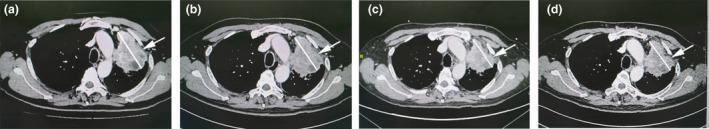

Circulating CAR-T cells accounted for 3.30% of the patient's peripheral blood T cells detected by FACS analysis during the first follow-up (Day +29). The chest CT scan showed subtle tumor shrinkage (stable disease). On Day +43, the patient developed pyrexia without any known causes and dyspnoea that rapidly deteriorated to respiratory failure in 3 days. The chest X-ray and CT scan showed bilateral extensive pulmonary infiltration in addition to the tumor silhouette on the left upper lung. The interleukin (IL)-6 levels in serum dramatically increased (> 100-fold). The patient was immediately transferred to the ICU where he received oxygen and intravenous infusions of tocilizumab and methylprednisolone. His symptoms rapidly improved and the pulmonary inflammation gradually resolved.